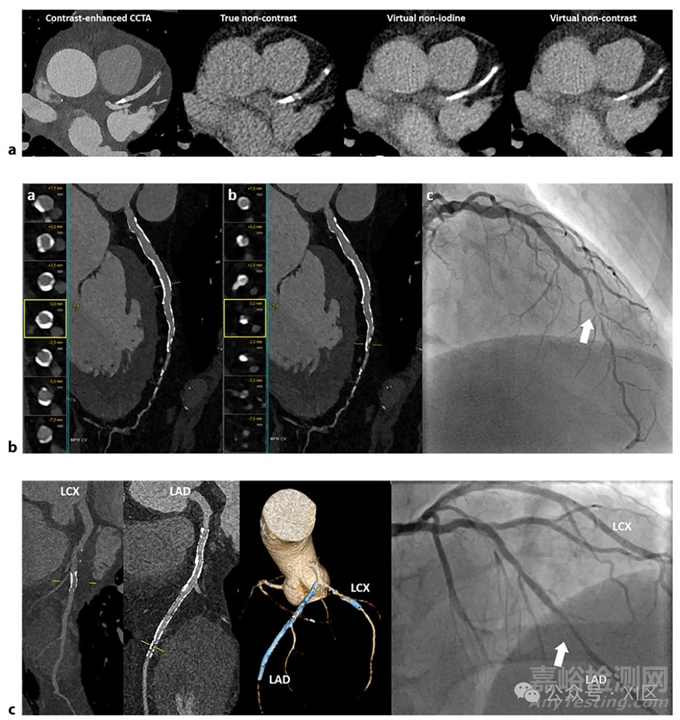

使用PCD-CT進(jìn)行的冠狀動(dòng)脈疾病高級(jí)評(píng)估。a 使用PCD-CT在增強(qiáng)、真實(shí)平掃、虛擬去碘和虛擬平掃圖像上進(jìn)行冠狀動(dòng)脈鈣化評(píng)分。與真實(shí)平掃圖像相比,左前降支(LAD)動(dòng)脈中的鈣化斑塊在虛擬去碘圖像上顯得更明顯,在虛擬平掃圖像上則不太明顯。b 對(duì)一名患有穩(wěn)定型心絞痛且存在多種危險(xiǎn)因素的66歲男性進(jìn)行冠狀動(dòng)脈超高分辨率成像。(a)LAD的多平面重建(MPR)圖像,顯示血管壁廣泛鈣化。MPR和橫斷面視圖顯示LAD近端和中段無(wú)明顯狹窄。(b)LAD的MPR圖像及橫斷面視圖顯示,LAD從中段到遠(yuǎn)端的過(guò)渡段管腔明顯變窄。(c)有創(chuàng)冠狀動(dòng)脈造影證實(shí)LAD中/遠(yuǎn)端存在明顯狹窄。c 使用超高分辨率PCD-CT進(jìn)行支架成像。對(duì)一名有典型胸痛癥狀的67歲男性患者采用超高分辨率模式的PCD-CT進(jìn)行冠狀動(dòng)脈CT血管造影。該患者有LAD和左旋支(LCX)動(dòng)脈支架置入史。多平面重建圖像顯示LCX支架通暢。然而,LAD支架內(nèi)遠(yuǎn)端存在再狹窄跡象。三維容積重建清晰顯示LAD和LCX中的支架。相應(yīng)的有創(chuàng)冠狀動(dòng)脈造影證實(shí)LAD存在支架內(nèi)再狹窄,LCX支架通暢。